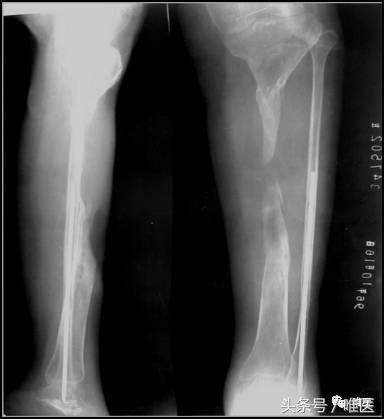

王某,女,20岁,车祸致左胫腓骨中上段开放骨折,外院多次手术后行走困难1年。

扶双拐行走,左小腿短缩,大片贴骨瘢痕,中上段明显异常动度,膝关节屈曲受限10~75度,肌力感觉无明显减弱。

3. X线片示

左胫骨中上段节段性骨缺损,断端骨质长节段萎缩,骨质硬化。